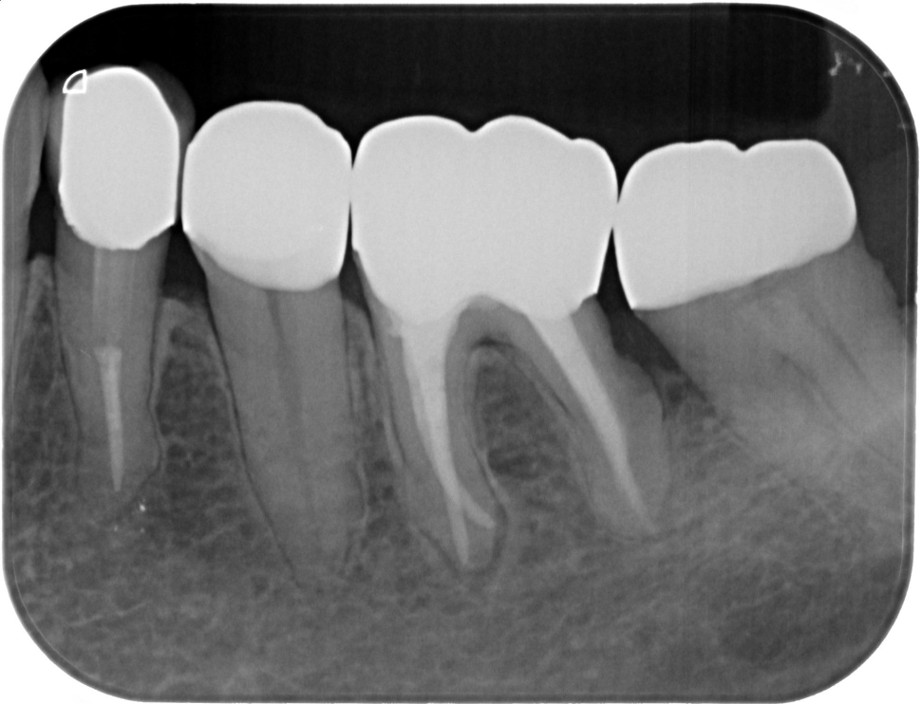

症例7

| 項目 | 詳細 |

|---|---|

| 患者様データ | 50代 男性 |

| 来院時の主訴 | 「右上の歯が噛むと少し痛い。」 |

| 医院の診断 |

虫歯の再発、未処置根管の存在 |

| 通院期間 | 4か月 |

| 来院回数 | 5回 |

| 治療費 | 220,000円(税抜) 《内訳》 精密感染根管治療80,000円、ファイバーポストコア20,000円、セラミック治療120,000円 |

| リスクと副作用 | ①根管治療歯は長期的には破折するリスク ②メインテナンスが必要 |

| ココがこだわりのポイント☝ |

上顎の小臼歯は1根か2根が通常ですが、この歯の場合なんと3根!それも途中で分岐しており4根管ありました。 これはかなりの確率で1%未満と思われます・・・術前のCT検査で発見されました。 そんな歯をラバーダム防湿とマイクロスコープを使用して丁寧に治療を行いました。 再根管治療のため、殺菌性があり歯を補強することのできる根管充填材料を使用しています。 |